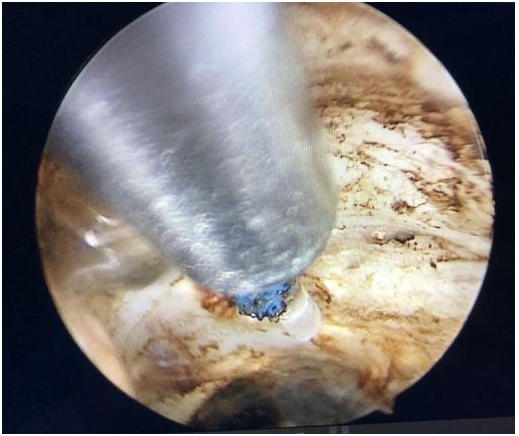

視察前列腺

沿前列腺包膜剜除